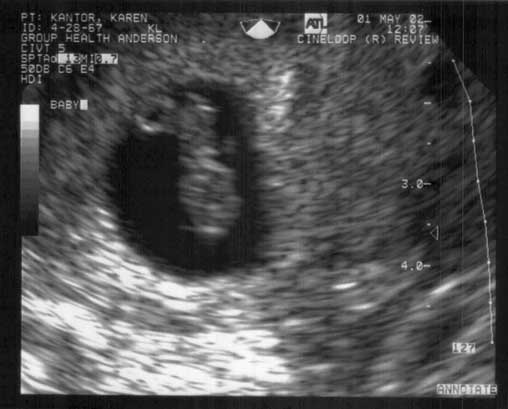

2002-0501 First-Ultrasound